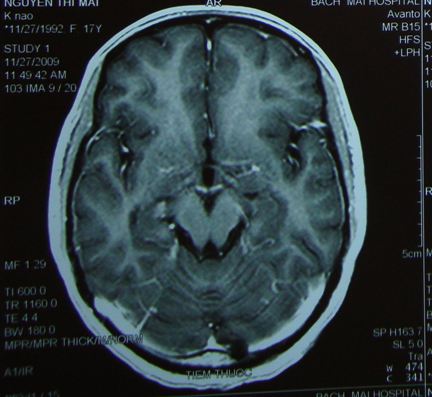

Trường hợp 2: Bệnh nhân Nguyễn Thị M. ,nữ 15 tuổi, vào viện vì lí do đau đầu, buồn nôn, nôn, thị lực 2 mắt giảm.

Trên film chụp cắt lớp vi tính sọ não và cộng hưởng từ sọ não thấy hình ảnh khối tổn thương choán chỗ vùng hố sau kích thước 3,5x3cm.

Bệnh nhi đã được chẩn đoán u não nghĩ nhiều là U nguyên bào tủy

Bệnh nhân đã được phẫu thuật lấy u tối đa, sau đó xạ trị gia tốc toàn não và tủy 36Gy, xạ trị bổ trợ thêm vào diện u để đạt liều xạ trị tại u là 56,8Gy.

Tiếp theo đó bệnh nhân được điều trị hóa chất 08 đợt

Hiện tại bệnh nhi hoàn toàn khỏe mạnh, không liệt, không đau đầu, không nôn bệnh nhi đã trở lại cuộc sống bình thường và đi học trở lại.

Trên phim chụp cộng hưởng từ toàn thân: không có tổn thương tái phát hoặc di căn.

Tổn thương u trước điều trị: khối u vùng hố sau kích thước 3,5x3cm

Sau điều trị, tổn thương u đã tan biến hoàn toàn